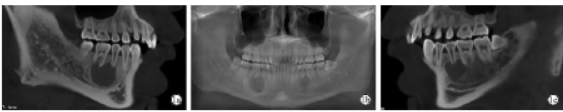

专科检查:患者面部基本对称,未触及颌下明显肿大淋巴结。口内检查见35、45牙齿畸形中央尖折断。35叩痛(-),45(±),无松动,冷热刺激未测,35、36、46牙髓电活力正常,45牙髓电活力消失。牙周检查无明显异常。牙龈黏膜无红肿,前庭沟黏膜色泽无明显异常,无触痛。CBCT 显示:左、右侧下颌骨35、36及45、46根尖区可见卵圆形囊性骨质密度减低影,边界清晰,颌骨未见明显膨胀,病变区牙根轻度吸收(图1)。血常规

图1 术前CBCT检查

。1a:右侧下颌骨囊肿;1b:双侧下颌骨囊肿曲面;